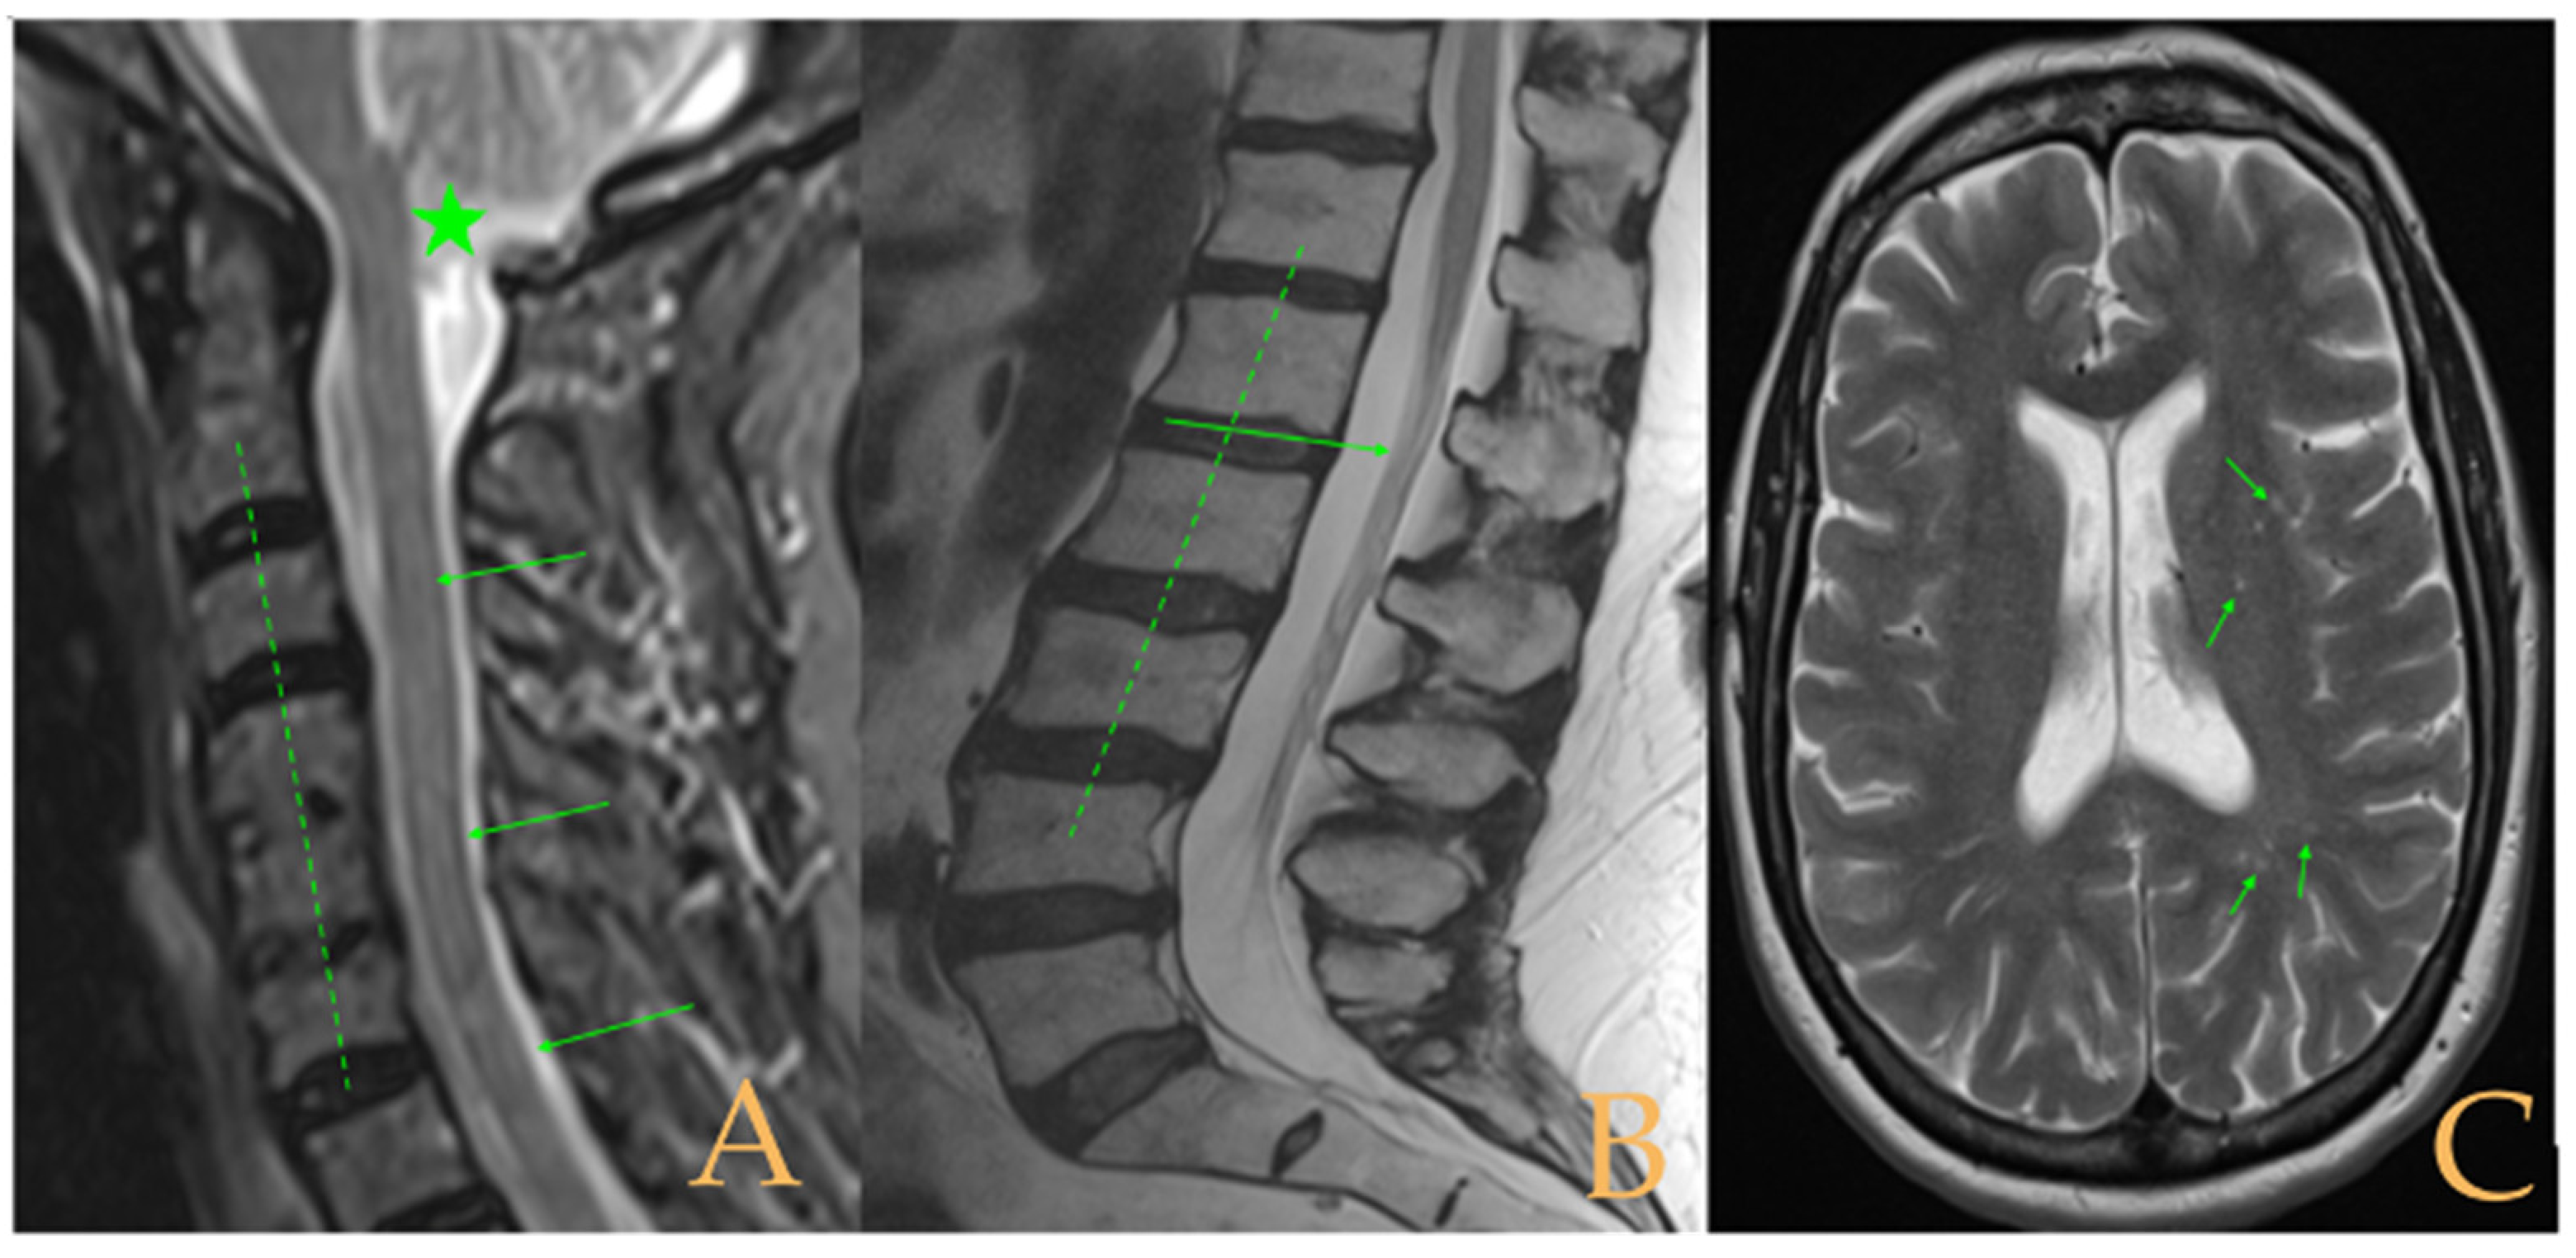

Magnetic resonance imaging (Figure 10) showed macro lacunae bilaterally in the frontal white matter. Postsurgical changes from occiput to C7. Fusiform intramedullary cyst at C7, with the rest of image showing ischemia/oedema in the cervical and thoracic cord with foci of intramedullary cyst. Multiple Schmorl’s hernias. Disc disease: T2-T3, T5-T6-T7, T10-T11-T12, L3-L4, and L5-S1. Straightening of cervical lordosis and thoracic kyphosis. Conus medullaris at level T12-L1. Lumbar laminectomy with interbody fusion and transpedicular screws L4-L5. The full-spine X-rays showed slight misalignment of the spine in the anteroposterior plane and loss of the cervical lordosis and thoracic kyphosis in the sagittal plane.

Figure 10. Imaging of patient 10. A: Macro lacunae in white matter (arrows); B: intramedullary cyst at C7 (arrow), arthrodesis C6C7 (star), and cervical straightening (interrupted line); and C: lumbar straightening (interrupted line), conus medullaris at T12L1 (arrow), and arthrodesis L4-L5 (star).